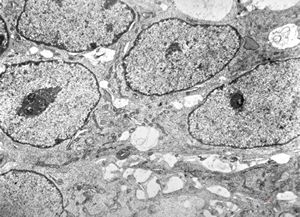

F,44y. | ependymoma

F,44y. | ependymoma

F,44y. | ependymoma

F,44y. | ependymoma